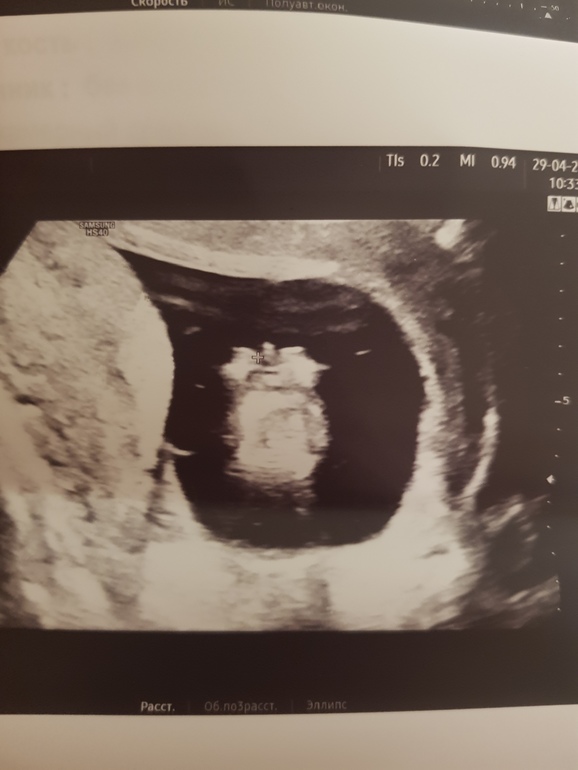

Помогите определить пол пожалуйста 12,4 недель фото узи

Здравствуйте дорогие мамки всем за ранее спасибо ,,,, вот узи 12,4 недель здесь есть опытные мамки у кого как было ,? Как думаете у нас принцесса будет или принц ????🙏🥰